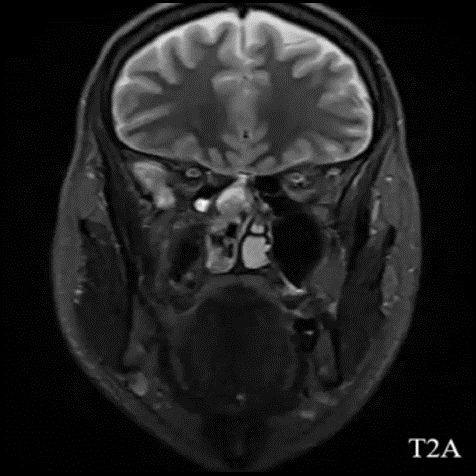

- A) Koronal T2A görntüde sağ süperior nazal kavite içerisinde hafif ekpansil karakterde, keskin sınırlı, nisbeten lobüle konturlu heterojen ara sinyal intensitye sahip yumşak doku lezyonu izleniyor (oklar).

- Estezionöroblastom görüntülemede tipik olarak nazal kavite tavanında, lamina cribrosa düzeyinden köken alan, etmoid sinüsler, orbita ve anterior kraniyal fossaya yayılım gösterebilen lobüle, agresif karakterli bir yumuşak doku kitlesi olarak izlenir ve sıklıkla komşu kemik yapılarda destrüksiyona neden olur. MR’da lezyon genellikle T1-ağırlıklı serilerde izo/hipointens, T2-ağırlıklı serilerde hiperintens sinyal özelliği gösterir ve kontrast sonrası heterojen güçlü kontrastlanma izlenir. İntrakraniyal uzanım varlığında tümör ile frontal lob parankimi arasında izlenen peritümöral periferik kistik değişiklikler, estezionöroblastom için literatürde tanımlanmış ayırt edici ve spesifik bir MR bulgusudur.

- Bununla birlikte görüntüleme bulguları her olguda tipik olmayabilir ve diğer sinonazal malignitelerle örtüşebilir. Bizim olgumuzda MR bulguları tipik özellikleri yansıtmamış olup, kesin tanı postoperatif histopatolojik inceleme ile estezionöroblastom olarak konulmuştur.